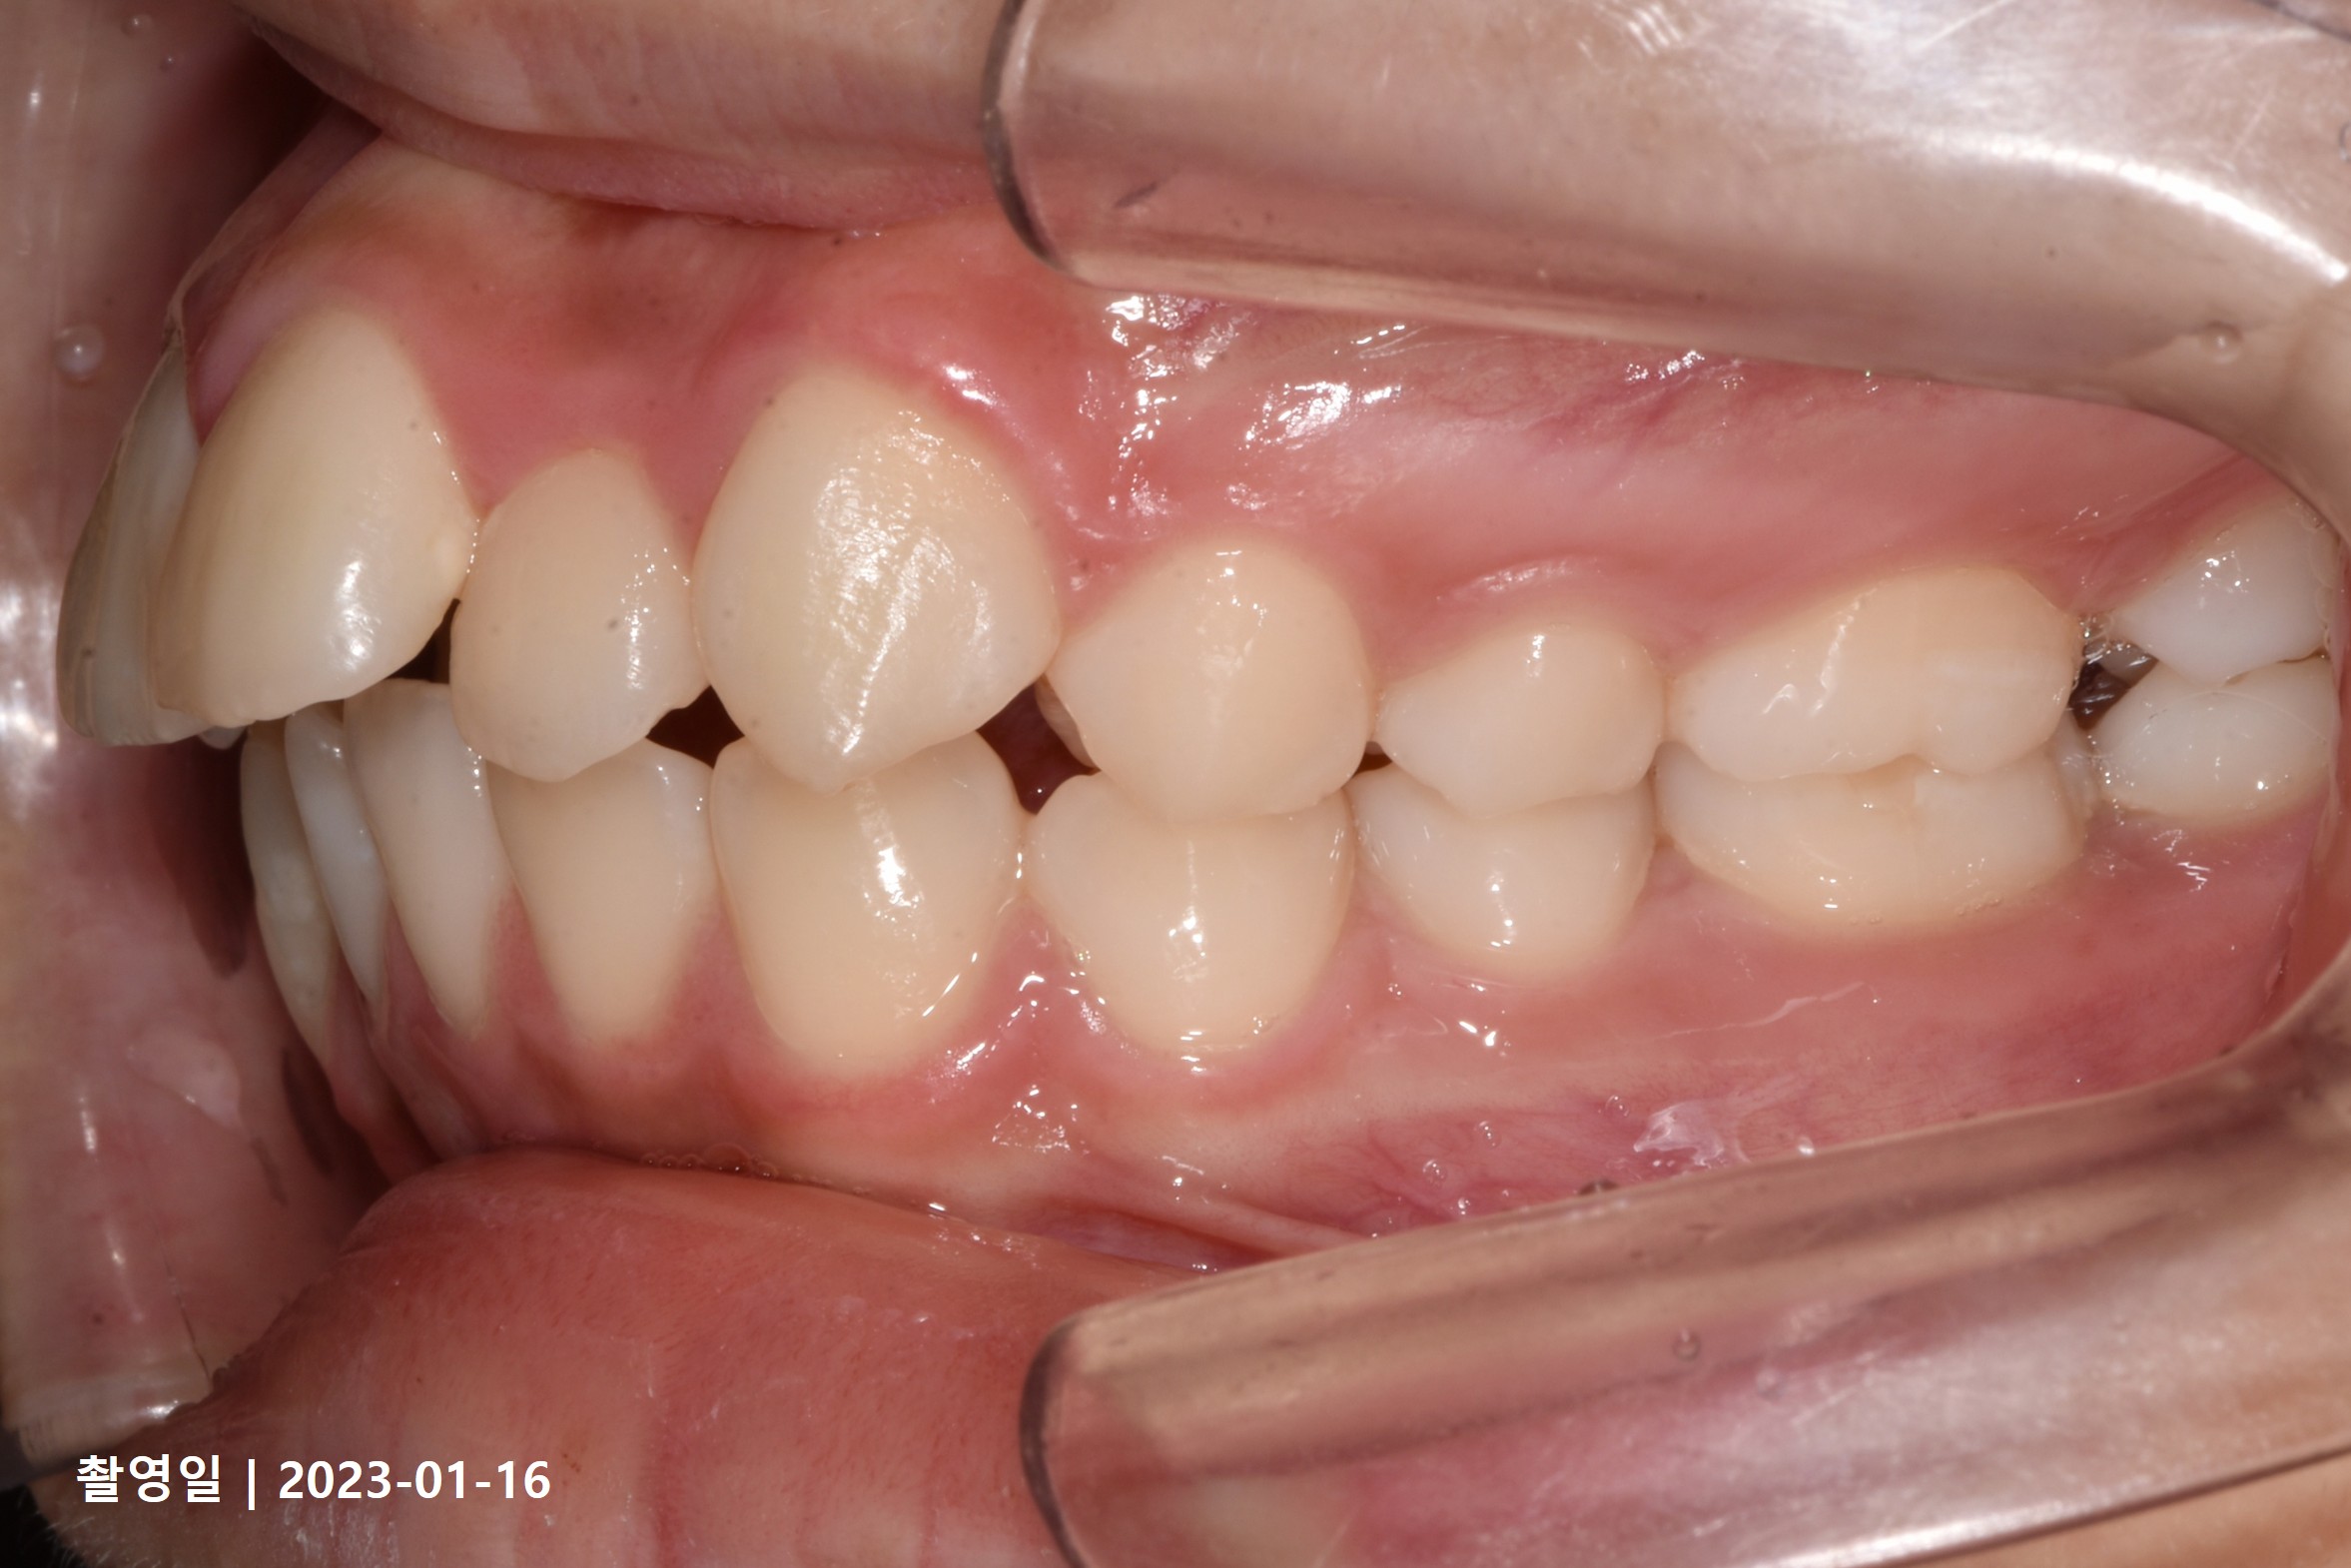

Case 4

- 19세 여성

- 상하악소구치 발치

- 치료기간 2년 8개월

치료 전

치료 후